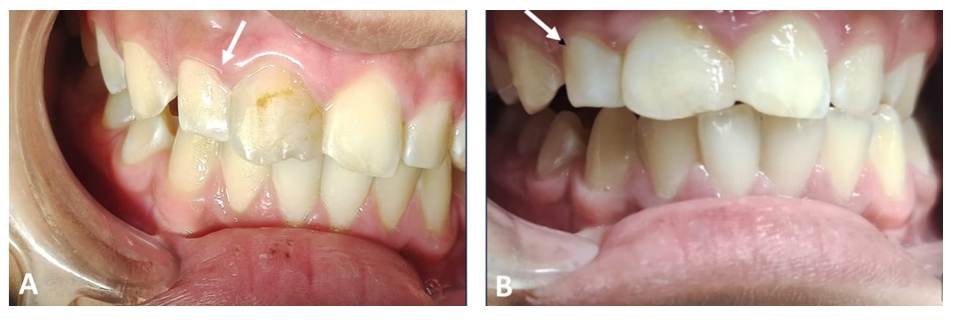

The patient did not report any painful symptoms during the 3-month rest treatment or at other follow-up visits. The case was clinically asymptomatic as all signs and symptoms had disappeared completely, and the gingiva appeared normal on follow‐up recall (Figure 3). Periapical radiographs show signs of healing of the periapical lesion, increasing radiopacity, and decreasing root divergence through follow‐up recall at 6, 12, and 18 months (Figure 4).

Figure 3 Clinical lateral views show the straightening of the tilted lateral incisor #12 (arrow) after two years (A) and complete treatment after restoration of the upper central incisor #11 (B).